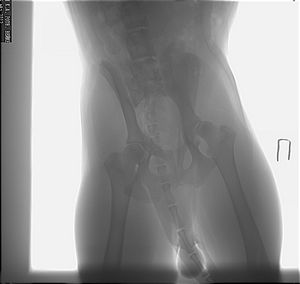

Даже при условии, что среди доберманов дисплазия встречается относительно редко, проблема максимально раннего выявления заболевания должна постоянно занимать владельцев и заводчиков, потому что речь идет о заболевании, при котором животное страдает, более того, может стать инвалидом. Необходимо как можно раньше диагностировать болезнь с тем, чтобы исключить возможность осложнений при неправильном выращивании щенка, усугубления болезни преждевременной вязкой, чтобы своевременно начать лечение.

Систематические спаривания и скрещивания, а затем обследования потомства лабораторных собак дали следующие результаты: